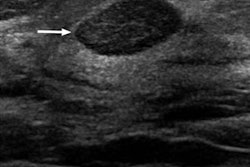

The study included 189 women with 196 lesions classified as clustered microcysts on breast ultrasound scans between 2005 and 2015. Any pathology or cytology report information gathered by ultrasound-guided biopsy was also considered. If no biopsy was performed, only lesions with at least two years of imaging follow-up were included. The mean maximum size of the lesions was 0.88 cm.

Of the 196 lesions, 158 (81%) were tracked with imaging over the course of 24 months; 38 (19%) were biopsied. The researchers found that none of the lesions were found to be malignant over the follow-up period. The team also found that of the 158 clustered microcysts with at least two years of imaging follow up, 73% were unchanged, 18% resolved, and 8% decreased in size.